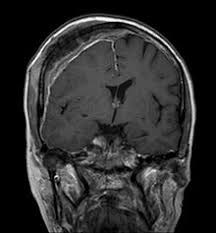

Glioblastom Neurochirurgie Inselspital Bern

Hirnmetastasen Neurochirurgie Inselspital Bern